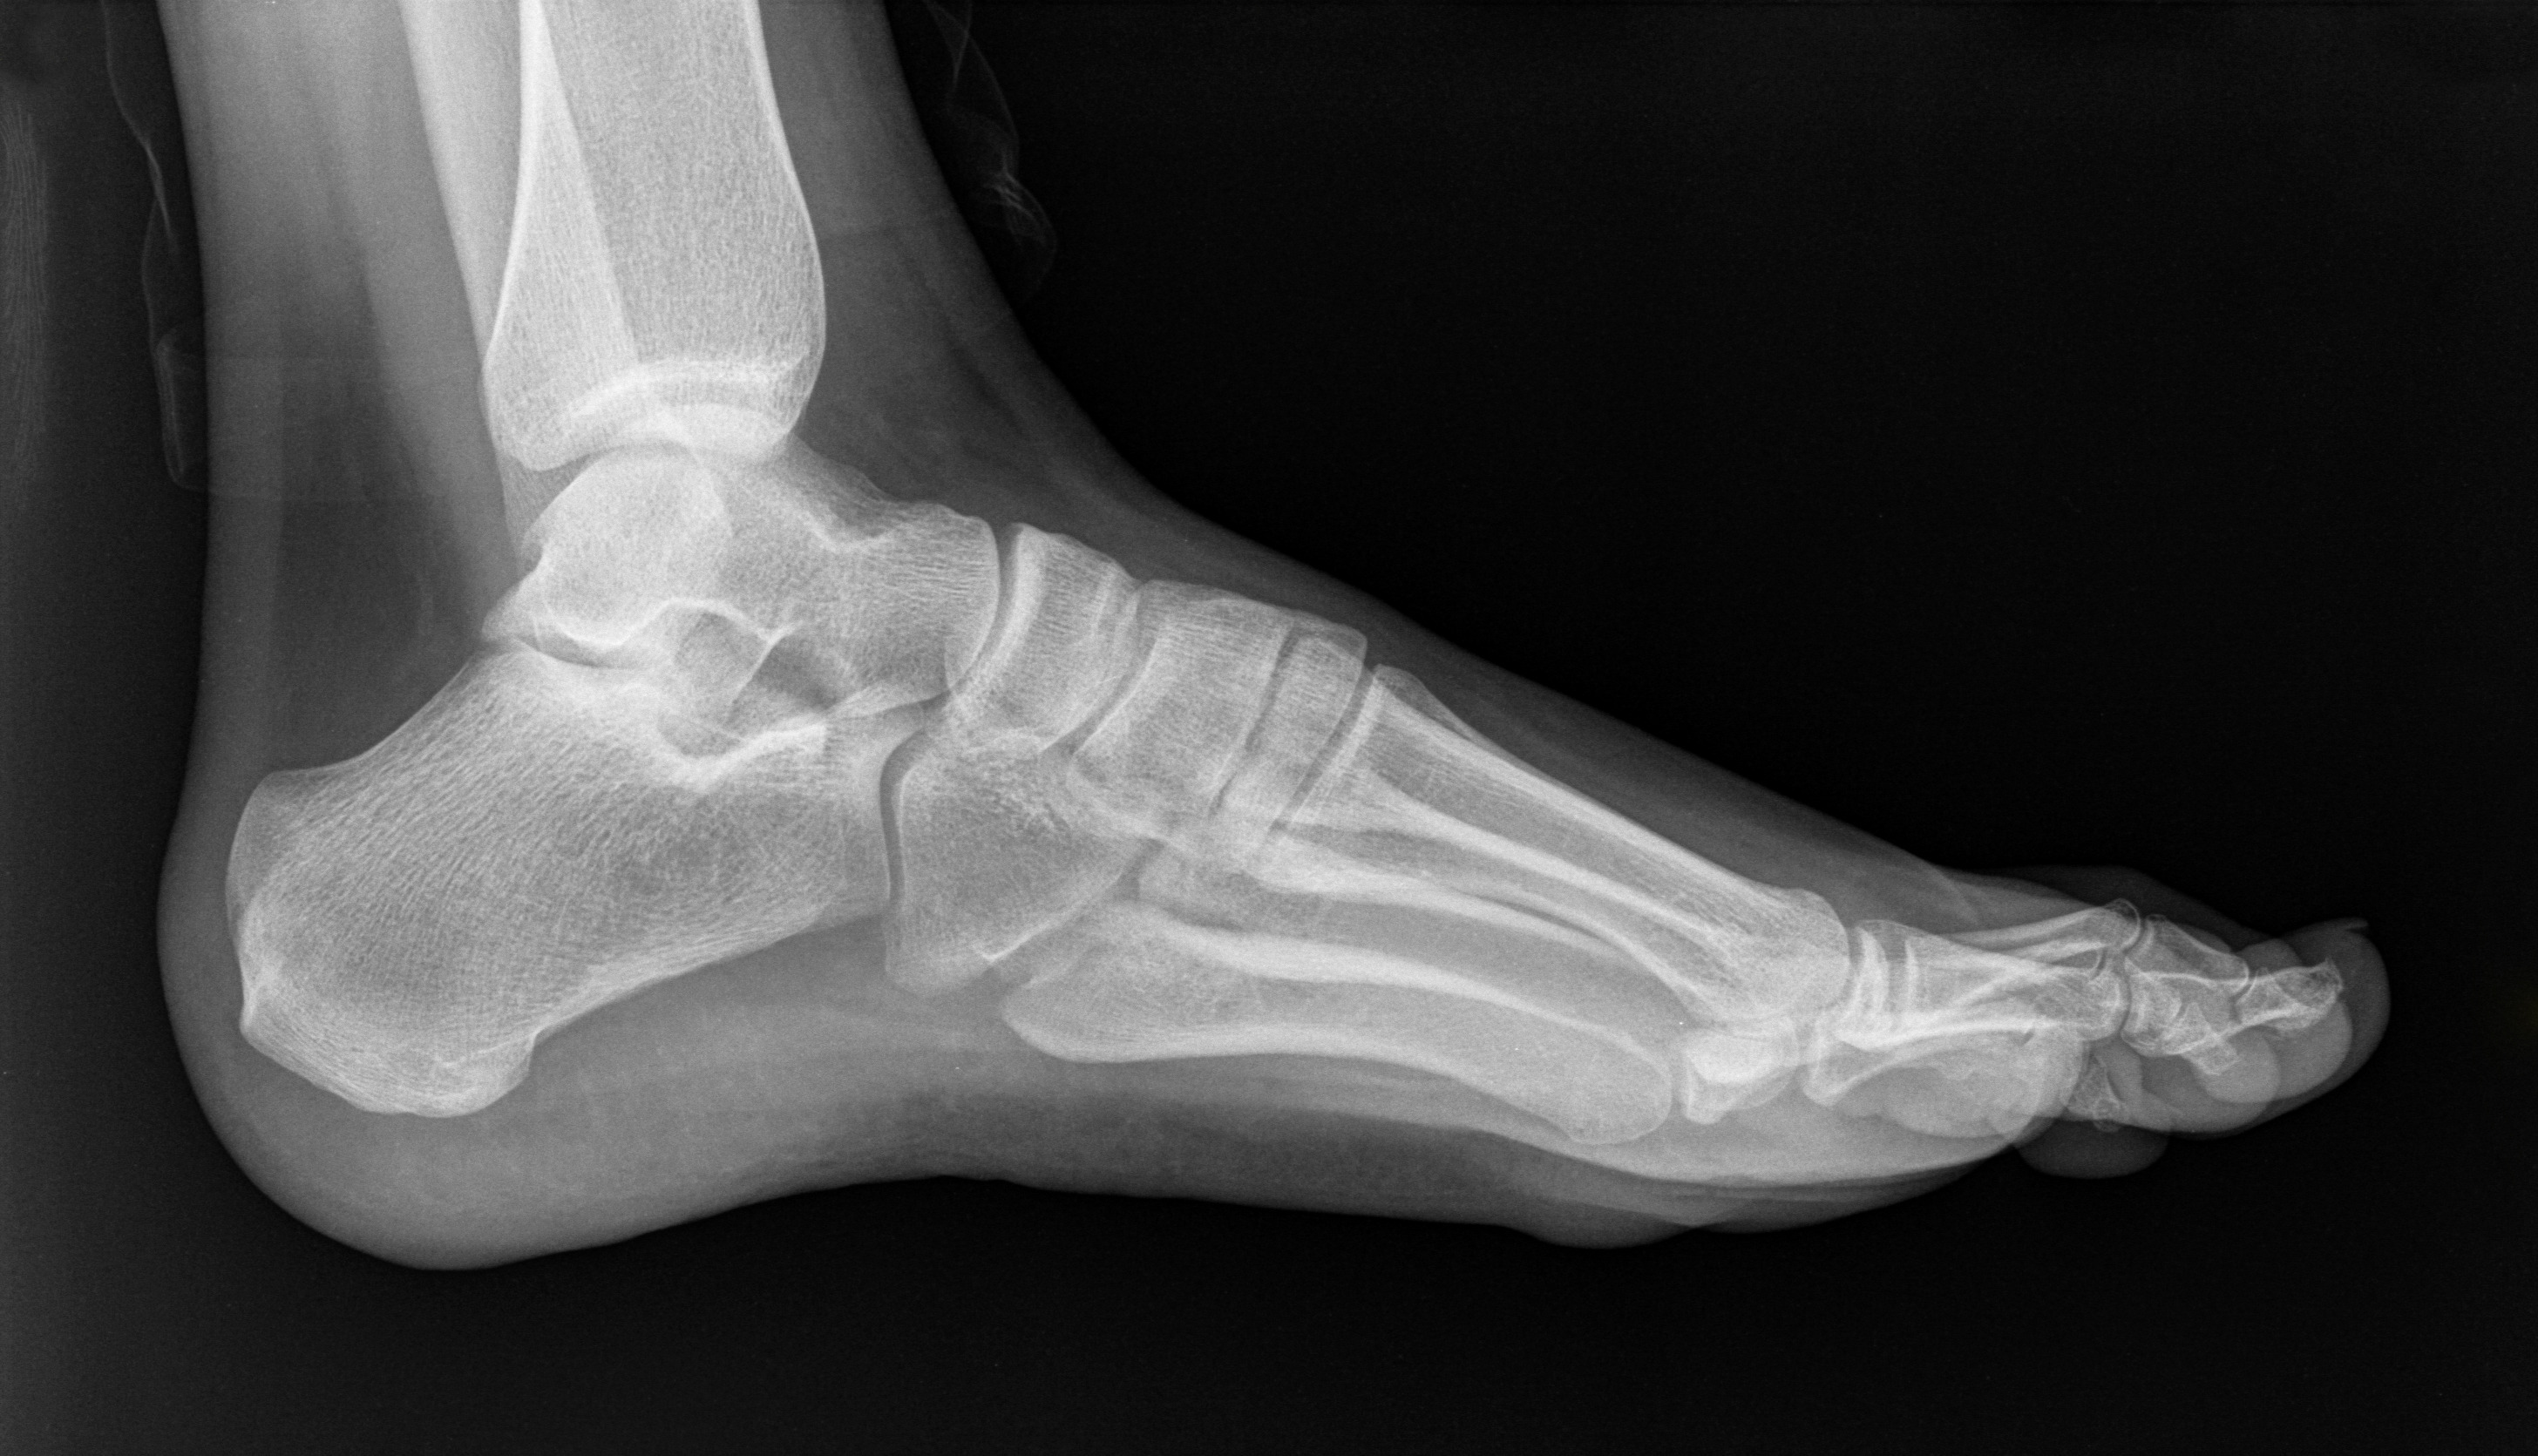

Сообщается, что каждый пациент, переболевший COVID-19, может заболеть остеонекрозом головки бедренной кости. Заболевание провоцирует нарушение кровоснабжения и вызывает разрушение костной ткани, что может привести к эндопротезированию.

Количество пациентов с ОНГБ в последние годы увеличилось. Патология встречается даже у тех, кто переболел коронавирусом в легкой форме.